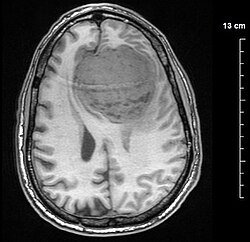

A meningioma is a tumor originating from the meninges, the protective membranes encasing the brain and spinal cord. Generally, these tumors exhibit slow growth and tend to be benign, yet their size and location can precipitate symptoms and complications.

Meningiomas do not adhere to brain tissue; they exhibit a distinct separation from the brain, enabling complete surgical removal. Typically, meningiomas measure under 2 cm; however, some can reach sizes of up to 5 cm, potentially encompassing a quarter of the brain. As the tumor enlarges, it increasingly jeopardizes brain functions, with its location further exacerbating potential negative impacts.

Meningiomas may reside in various regions of the brain silently, exhibiting no symptoms. However, once symptoms manifest and raise suspicion of meningioma, diagnosis typically involves utilizing brain MRI and computed tomography scans.